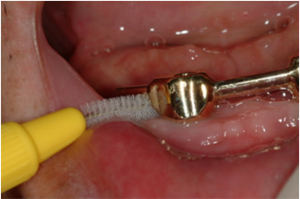

큰 문제란, 임플란트 주위의 잇몸에 염증이 발생하여 임플란트 주변골이 파괴되고 더 나아가 임플란트가 흔들리게 되는 경우를 말합니다. 이를 막으려면 적절한 임플란트 시술과 함께 환자분의 충분히 깨끗한 칫솔질이 필요합니다. 큰 문제가 없더라도, 임플란트의 상부 보철물에 여러가지 작은 문제점 (나사풀림, 도재파절, 음식물침착의 증가 등)들이 발생할 수 있으나 이는 상부보철물의 수정 또는 교체를 통해 치료 가능하므로 임플란트 자체는 계속 사용하실 수 있습니다.

치료 종료 후 연1회의 정기적인 검진은 이러한 크고 작은 문제점들을 조기에 발견하고 예방하는데 큰 도움이 되므로 반드시 필요합니다.